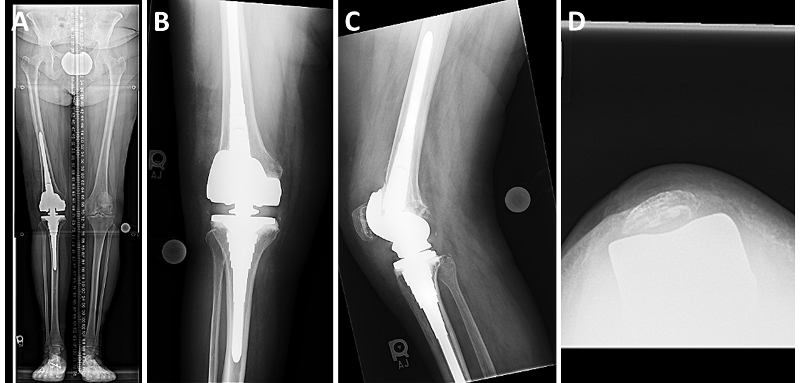

In this patient, we used single-dose postoperative radiation to prevent recurrence of arthrofibrosis. At four weeks postoperatively, her wound had healed. She achieved full knee extension and flexion to 90 degrees. Her radiographs show excellent alignment in the coronal plane and improved patellar tracking (Figure 2A-D).

Fig. 2